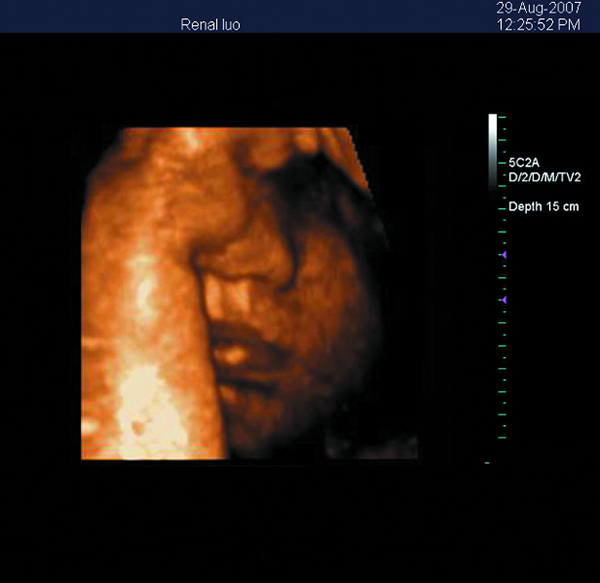

| 6. | 3D imaging(option) |

| 5. | 3D imaging software | 1 set |

Images

Portable Color Doppler Ultrasound Machine With Measurements And Calculations Software Images |